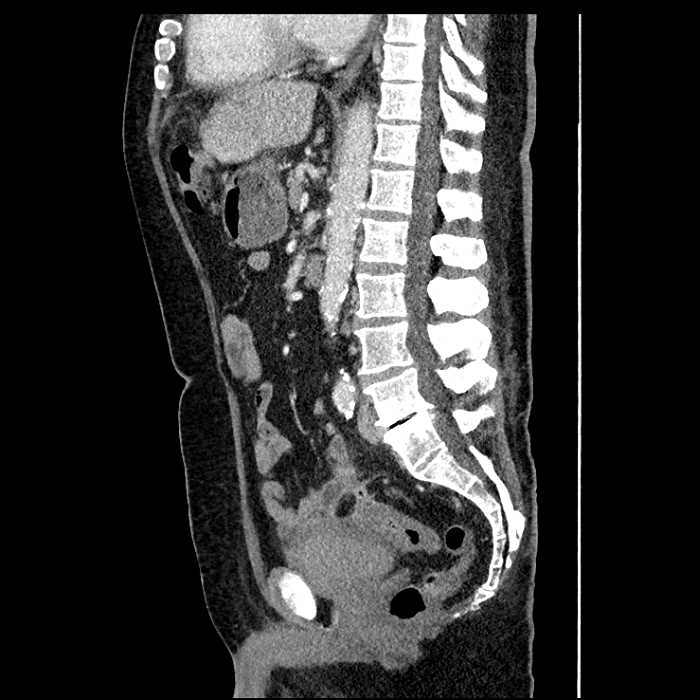

• Large fluid density structure in hepatic segments 7 and 8 measuring 10 x 7 x 7 cm with internal septation and circumferential ill-defined low density compatible with edema

• Peripherally enhancing subcapsular collections along the anterior margin of the left hepatic lobe measuring 3 x 1 cm and 2 x 1 cm

• Clearly marginated fluid density structure in segment 7 and several other scattered tiny hypodensities, which likely represent cysts

• High grade stenosis of the left common iliac artery, with the left internal and external iliac arteries remaining patent

Acute sigmoid diverticulitis complicated by a small contained perforation and a large abscess in the right hepatic lobe. Additional small subcapsular abscesses along the anterior margin of the left hepatic lobe.

• The classic CT imaging appearance is a double target sign with internal low density surrounded by an internal enhancing rim (capsule) and a low density external rim (edema)

Hepatic abscess showing the double target sign with low density internally surrounded by a thin inner enhancing rim (red arrow) and ill-defined outer low density rim (yellow arrow). Blue arrow indicates an internal septation. Red arrows: additional smaller subcapsular abscesses. Red arrow: focal contained perforation associated with diverticulitis.